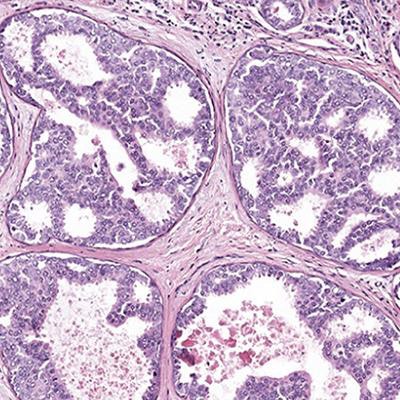

An AI system outperformed doctors in differentiating DCIS (pictured) from atypia, one of the more challenging diagnoses in breast cancer cases. Image courtesy of Elmore Lab/UCLA.

An AI system outperformed doctors in differentiating DCIS (pictured) from atypia, one of the more challenging diagnoses in breast cancer cases. Image courtesy of Elmore Lab/UCLA.It's estimated that more than 1 million people in the U.S. will get a breast biopsy this year, and the diagnosis and treatment of early-stage lesions that would never actually become breast cancer, including types of DCIS, has long been a concern.